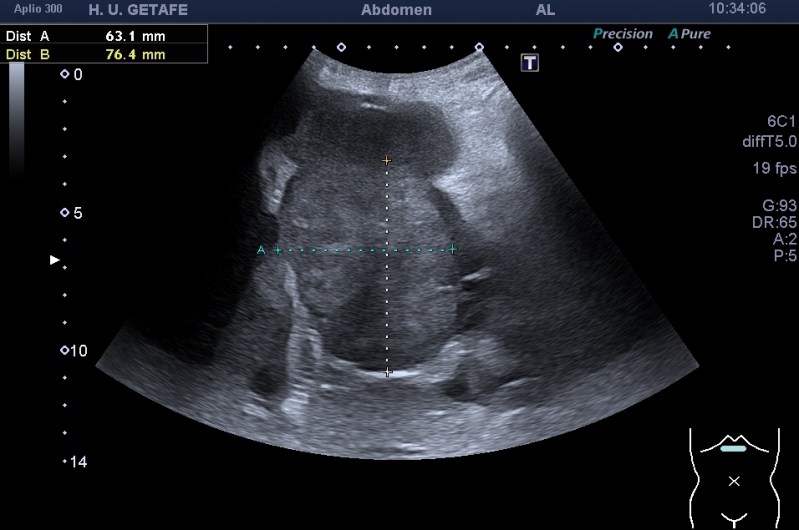

Dentro de los estudios del abdomen estudiamos siempre la vía biliar intra y extrahepática, lo he contado en Post anteriores y está más que revisado. El caso de hoy es distinto. Dentro de un estudio de abdomen exploramos la región de la vía biliar con el objeto de localizar y certificar el posicionamiento no migrado de una endoprotesis biliar.

El estudio certificó que el Stent estaba bien posicionado y que el avance de la enfermedad mostraba una gran masa sólida hepática que sería la responsable de la nueva aparición de la ictericia.

Te enseño imágenes:

La endoprótesis se observa como una ecoarquitectura hiperecogénica con un entramado típico de los stents que se colocan en otras localizaciones cardiacas o aórticas. Se puede observa el aspecto rejilla típico, rodeado de una estructura hiperecogénica que es el cuerpo de la malla y que combate el aumento de la presión producida por el crecimiento de la masa tumoral.